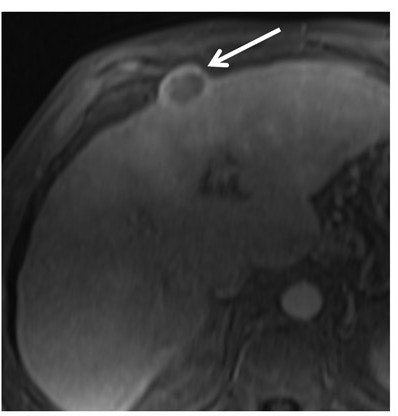

To help fill that void, Mulé and colleagues performed a retrospective study to analyze 152 patients (median age, 64 years; range, 56-72 years) who preoperatively underwent a liver scan with either 1.5-tesla (Avanto, Siemens Healthineers) or 3-tesla (Skyra, Siemens) MRI. Each patient had one HCC lesion, which subsequently was treated with surgical resection. Among those subjects, MRI identified 26 macrotrabecular-massive HCCs (17%).

They determined that substantial necrosis (occupying at least 20% of the tumor), high serum AFP levels (> 100 ng/mL), and BCLC stage B or C cancer were independent predictors of macrotrabecular-massive HCC subtype:

- Through substantial necrosis, 17 macrotrabecular-massive HCCs (65%) were identified, with specificity of 93%.